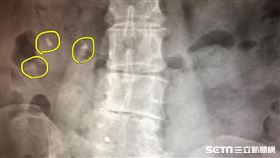

罕見!醫驚見「3顆睪丸伯」:90歲還掛外面

男性睪丸主要作用為產生精子及分泌雄性激素睪固酮,一般...